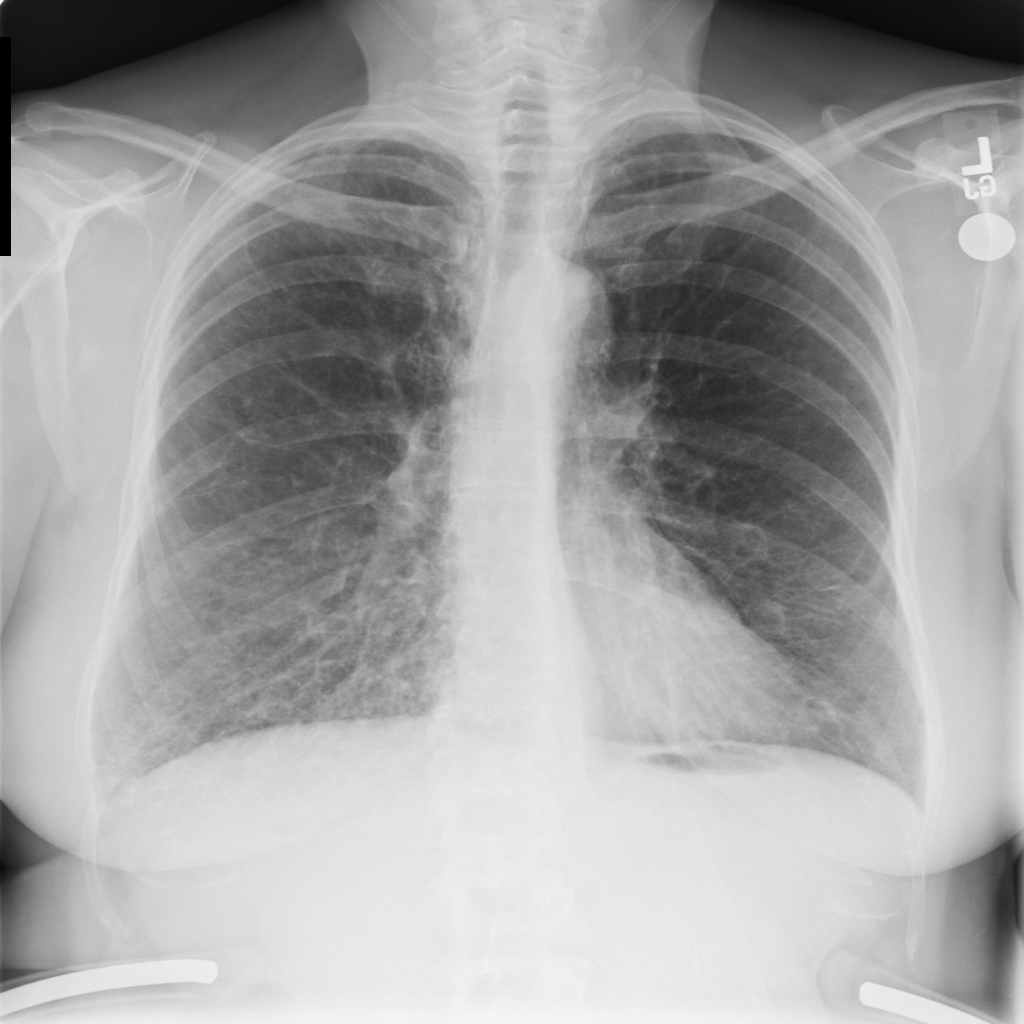

PAT-E066 · IMG-010Fibrosis

PAT-E066 · IMG-010

PA